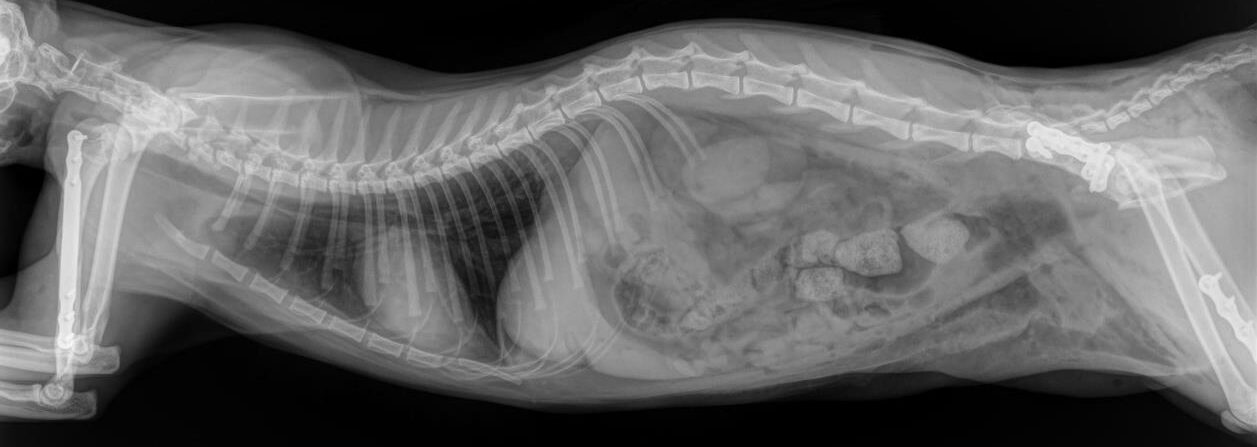

Day 1: He had to fix a humerus spiral fracture (left) with a LeiLOX bridge plate. Furthermore, he diagnosed a femur transverse fracture. Dr. Sonntag then used a 7-hole LeiLOX plate to repair this fracture, and do several emergency soft tissue surgeries.

(Surgery time: 1:15 hours)

Day 2: Repair of two iliac bone traverse fractures (left and right) with LeiLOX L-plates. Finally, several soft tissue surgeries were performed.

(Surgery time: 1:50 hours)